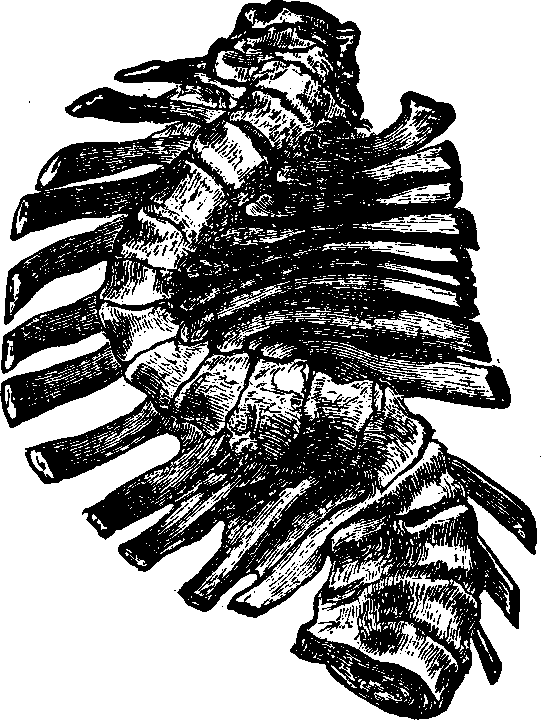

The Trunk has fifty-four bones, which are as follows: The Os Hyoides, the Sternum, twenty-four Ribs, twenty-four vertebræ or bones of the Spinal Column, the Sacrum, the Coccyx, and two Ossa Innominata. The Os Hyoides, situated at the base of the tongue, is the most isolated bone of the skeleton, and serves for the attachment of [pg 24]muscles. The Sternum, or breast-bone, in a child is composed of six pieces, in the adult of three, which in old age are consolidated into one bone. The Ribs are thin, curved bones, being convex externally. There are twelve on each side, and all are attached to the spinal column. The seven upper ribs, which are united in front of the sternum, are termed true ribs; the next three, which are not attached to the sternum, but to one another are called false ribs; and the last two, which are joined only to the vertebræ, are designated as floating ribs. The first rib is the shortest, and they increase in length as far as the eighth, after which this order is reversed.

The Spinal Column or backbone, when viewed from the front presents a perpendicular appearance, but a side view shows four distinct curves. The bones composing it are called vertebræ. The body part of a vertebra is light and spongy in texture, having seven projections called processes, four of which are the articular processes, which furnish surfaces to join the different vertebræ of the spinal column. Two are called transverse, and the remaining one is termed the spinous. The transverse [pg 25]and spinous processes serve for the attachment of the muscles belonging to the back. All these processes are more compact than the body of the vertebra, and, when naturally connected, are so arranged as to form a tube which contains the medulla spinalis, or spinal cord. Between the vertebræ is a highly-elastic, cartilaginous and cushion-like substance, which freely admits of motion, and allows the spine to bend as occasion requires. The natural curvatures of the spinal column diminish the shock produced by falling, running or leaping, which would otherwise be more directly transmitted to the brain. The ribs at the sides, the sternum in front, and the twelve dorsal bones of the spinal column behind, bound the thoracic cavity, which contains the lungs, heart, and large blood-vessels.